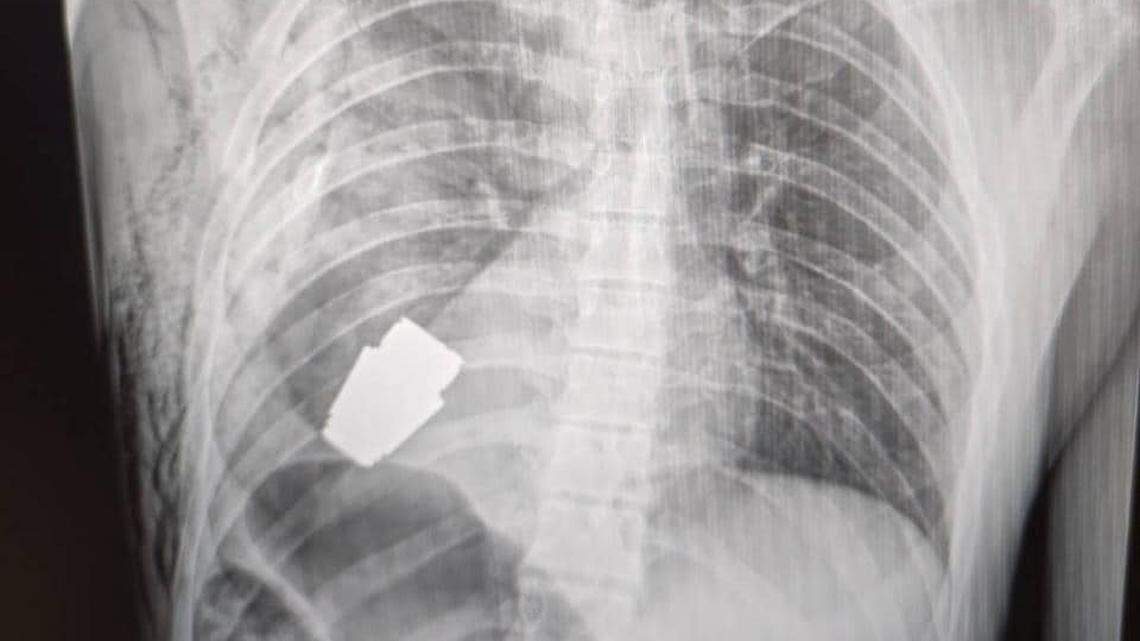

Photo from Ukrainian Deputy Defense Minister Hanna Maliar

The high-stakes operation removed an unexploded VOG grenade from the body of a Ukrainian soldier, Ukrainian deputy defense minister Hanna Maliar said in a Jan. 9 news release. X-rays show the grenade lodged in the soldier’s chest.

The unexploded part of the grenade was stuck under the soldier’s heart, adviser to the Ukrainian Ministry of Internal Affairs, Anton Gerashchenko, said in a Telegram news release.